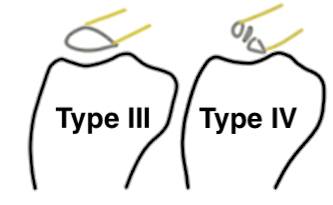

Meyers & McKeever classification

Type I: Undisplaced

Type II: Partially displaced with anterior portion hinged

Type III: Completely Displaced

Zaricznyj Type IV: Comminuted